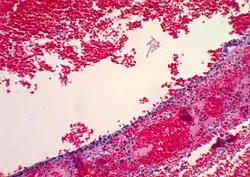

Histopathology

In case an ovarian cyst is surgically removed, a more definite diagnosis can be made by histopathology:

Type Subtype Typical microscopy findings Image

Functional cyst Follicular cyst

Corpus luteum cyst